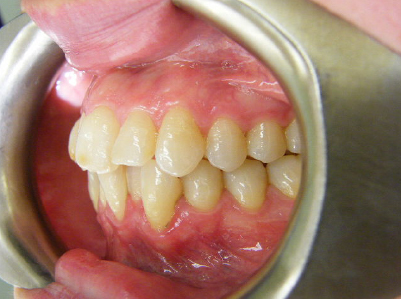

Patient 1: Severe upper and lower crowding with congenitally missing two lower adult teeth and a crossbite.